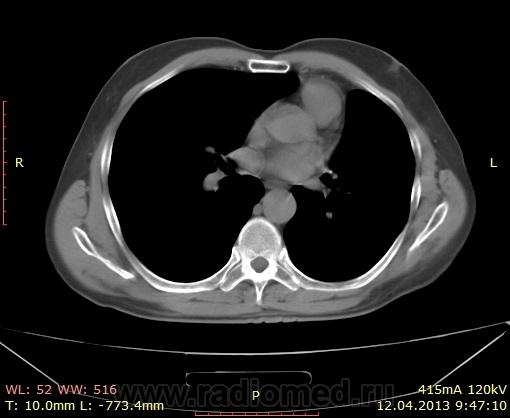

В апреле 2013 года снова прошел компьютерную томографию. Врач сделал следующее заключение:

крупная солитарная буллезная киста левого легкого, имитирующая пневмоторакса. КТ не демонстрировала рецидивного рака легкого, метахронного легочного рака, медиастинальной лимфаденопатии т.е. отсутствует возврат болезни, отсутствует плевральный выпот или pleurits.

Все снимки КТ от апреля 2013 г.